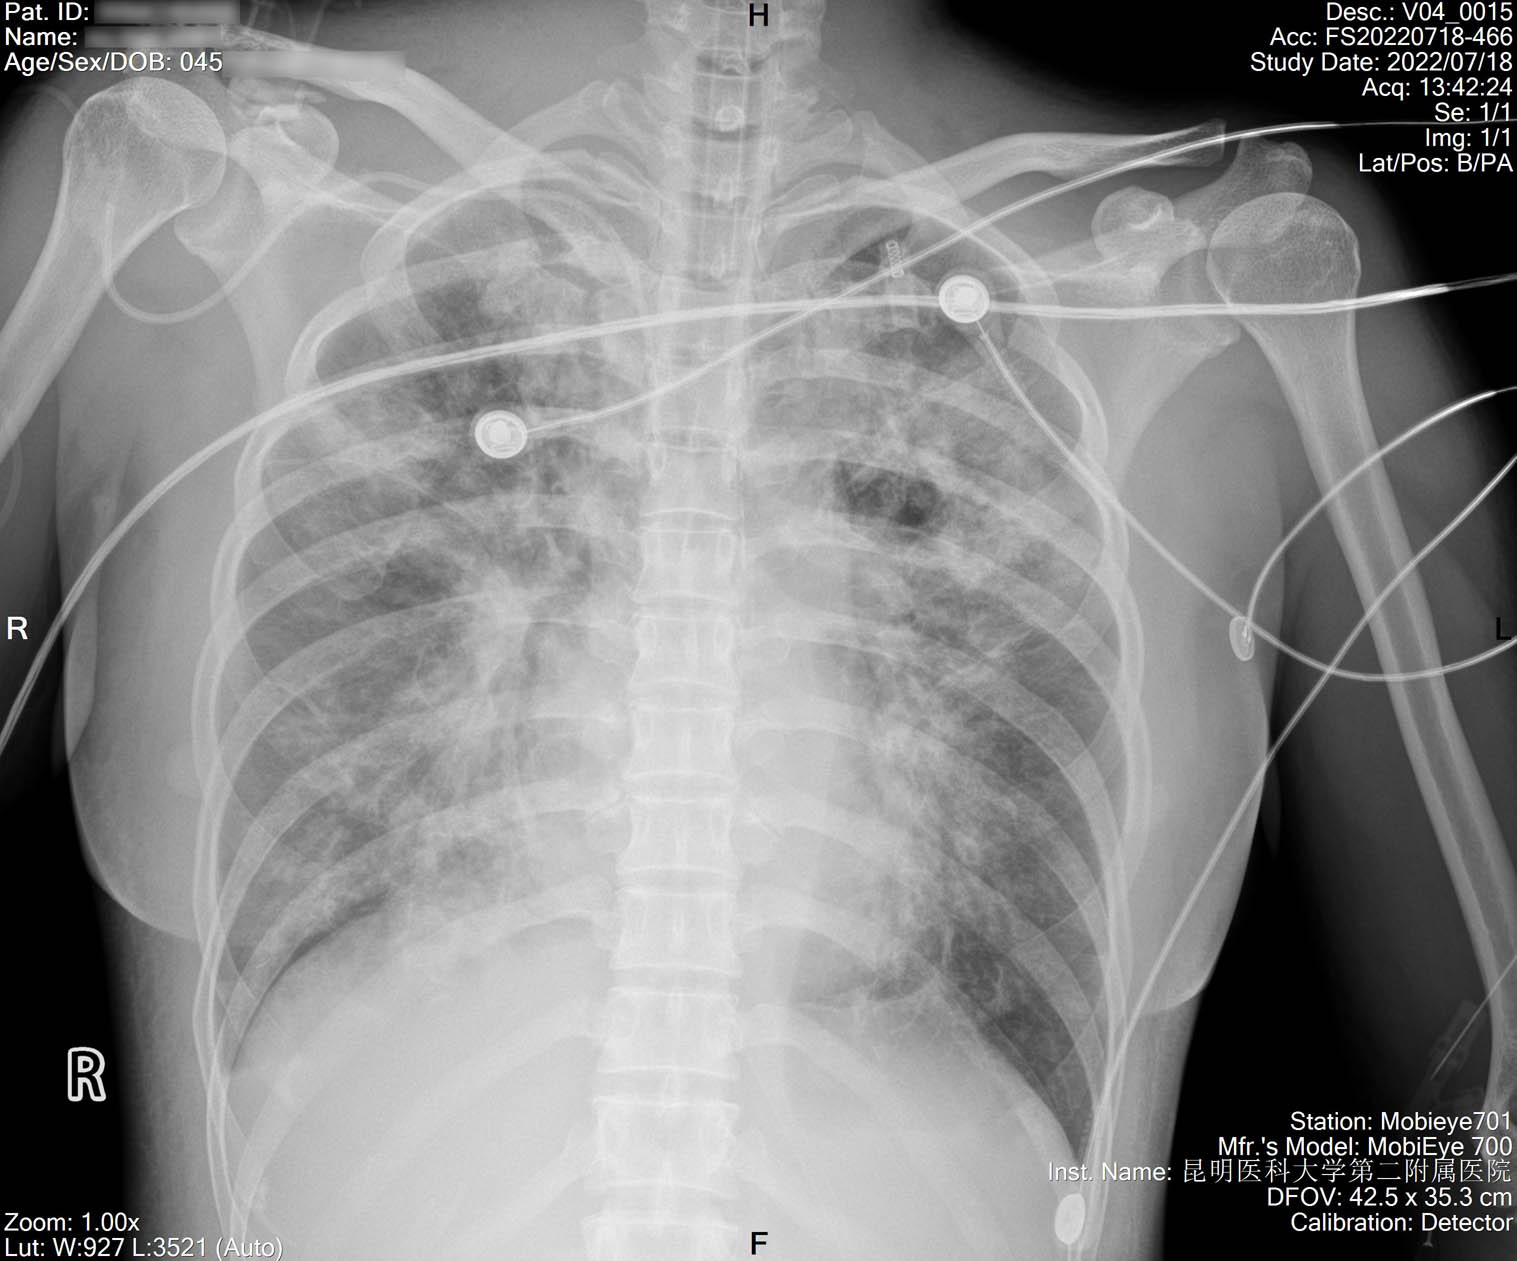

2022-07-18_胸片